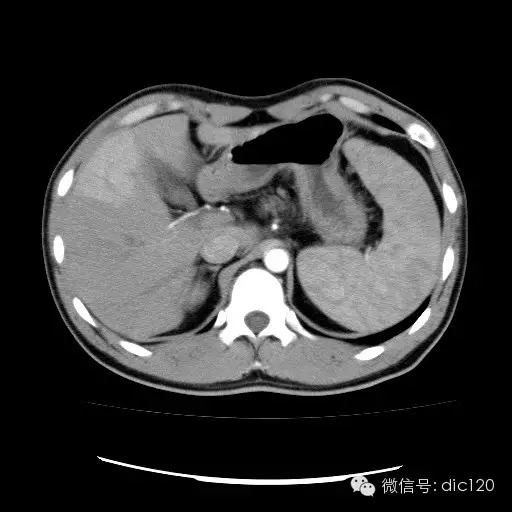

| 影像表现及分析: | 影像表现:动脉期扫描肝右叶紧贴边缘见一过性楔形高密度强化区,边界清,边缘平直,临近血管走形自然,门静脉期期恢复正常肝实质密度,延迟保持与肝实质密度一致。 |

| 疾病总结: | 正常肝脏的双重血供并非2个独立系统,两者之间有许多交通吻合,包括①肝窦间通路.②脉管间途径.③血管丛途径,即胆管周围血管丛途径.当肝脏发生血供障碍时,通过神经一体液因素的调节这些交通吻合支开放,双重供血发生血流量的变化甚至血流方向的改变.肝脏的这种”一过性”灌注异常在SCT表现为肝动脉期一过性肝实质强化(THPE).一过性肝实质强化差异是SCT增强扫描于肝动脉期表现的肝脏一过性灌注异常,大多数情况下它反映了局部肝脏双重血供的重新分布,即局部肝实质门静脉或肝静脉血流量减少,肝动脉血流量增多或为肝动脉门静脉分流或局部肝脏的变异或迷走血供所致。典型CT表现为肝动脉期一过性楔形或三角形高密度强化区,边缘平直,常位于肝脏边缘部位,其中血管走行正常,门静脉期恢复为正常肝实质密度。放射学医师应加强对一过性肝实质强化CT表现的认识。 |